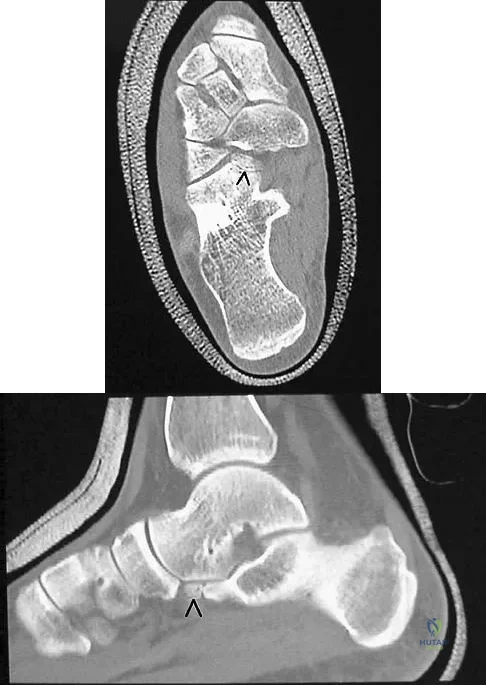

A 26-year-old rugby player injured his foot when tackled from behind. Radiographs are seen in Figures 35a through 35c. What is the most appropriate treatment?

The patient has a ligamentous Lisfranc injury. Diastasis seen between the bases of the second metatarsal and medial cuneiform is pathognomonic for a rupture of the Lisfranc's ligament. This injury is best treated surgically with either open reduction and internal fixation or possibly closed manipulation and percutaneous screw fixation if anatomic alignment can be achieved closed. Pin fixation has been shown to be inferior to screw fixation due to the length of time that fixation is required for adequate ligament healing. Chiodo CP, Myerson MS: Developments and advances in the diagnosis and treatment of injuries of the tarsometatarsal joint. Orthop Clin North Am 2001;32:11-20.